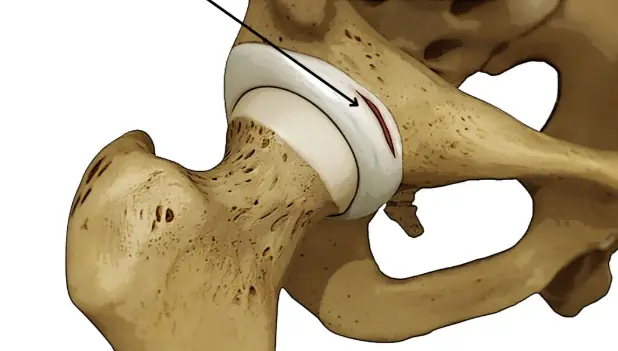

고관절이나 골반 통증이 지속되거나 일상생활에 불편함이 느껴지신다면, 전문적인 진단과 치료를 받아보시는 게 좋아요.

특히, 이상근증후군, 고관절 와순 손상, 석회성 건염 등 다양한 원인에 대해 세심한 진찰과 함께 부인과적, 내과적 문제까지 고려하는 종합적인 접근이 강점입니다.